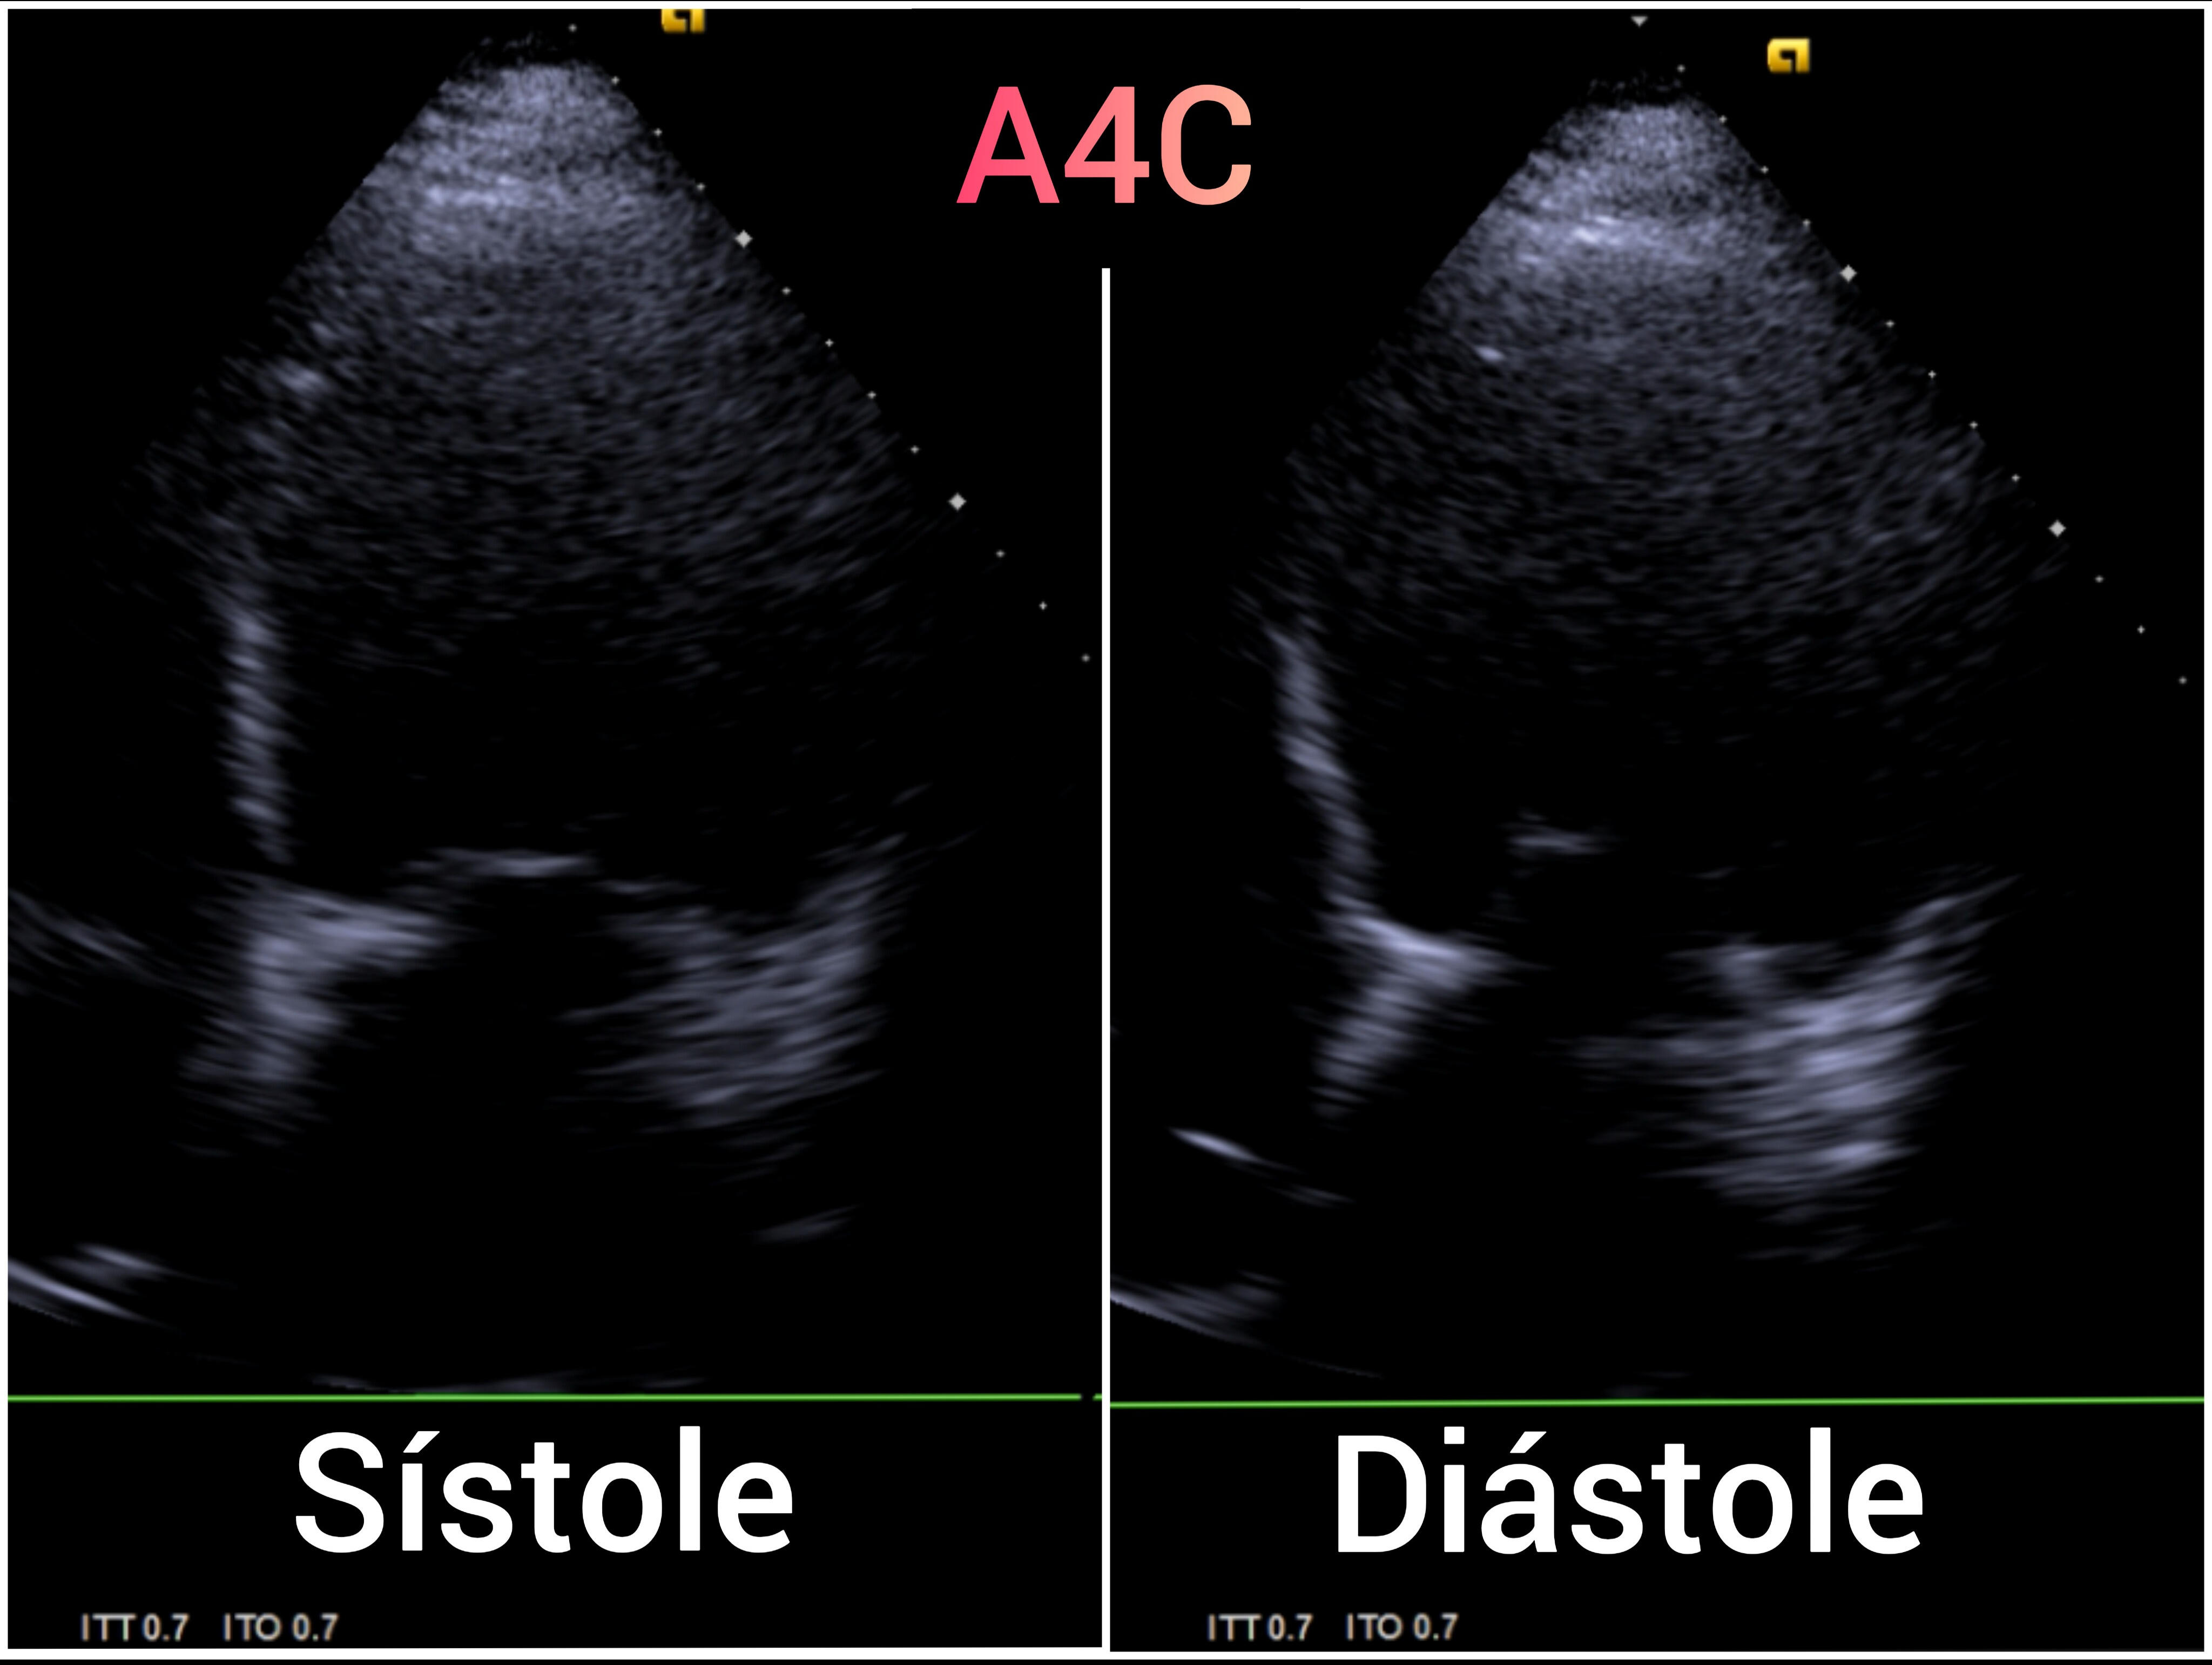

EcoCardioscopia: Mejoría de contractilidad subjetivamente respecto a previo, cavidades izquierdas dilatatadas tanto VI como AI.

Desde la última descompensación por IC el paciente mantiene aceptable tolerancia al ejercicio, cumplimiento terapéutico no así en tóxicos, congruente con los hallazgos de ecocardioscopia. Ante antecedentes familiares de cardiopatía, alteración genética y deseo de descendencia, remitimos de nuevo a Genética. Ademas, recomendamos estudio genético de la madre y la hermana.